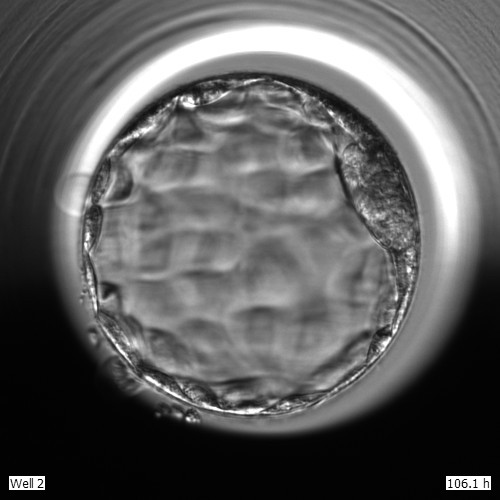

Det finns flera metoder för de som behöver hjälp att bli gravida. Vilken metod som passar bäst beror på förutsättningar hos den enskilda individen. En metod inom provrörsbefruktning, IVF, är när ett eller flera embryon, utöver det embryo som återförs färskt, fryses ner fem dagar efter befruktning. När kvinnan ska få en ny behandling förs ett tinat embryo in i livmoderhålan. Det är så många som drygt 40 % av kvinnorna som föder barn efter en lyckad behandling med frysta embryon.

- Det här en metod som är bra att använda för kvinnor där vi får flera befruktade ägg som utvecklats fint i fem dagar. Tidigare frös vi ner äggen redan ett par dagar efter befruktning. Nu har vi möjlighet att följa det befruktade äggets utveckling lite längre och då också sortera bort eventuella ägg som inte utvecklas som de ska vilket innebär att vi endast fryser embryon som håller en hög kvalitet, berättar Therese Bohlin som är laboratorieansvarig vid fertilitetsenheten vid USÖ.